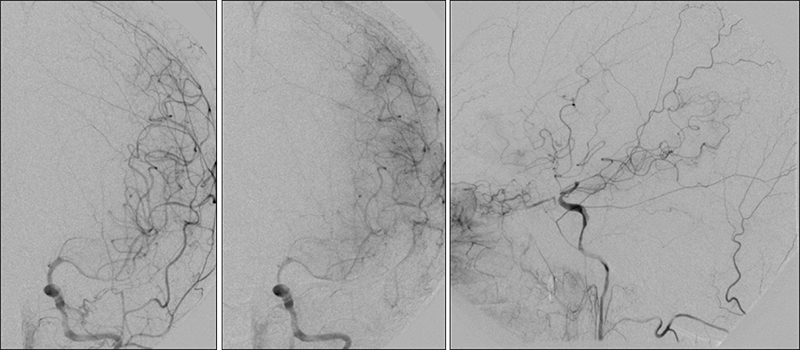

Εικόνα 7: Παρότι η αριστερή πλευρά είναι συμπτωματική, η παρουσία προσφάτων θρόμβων στον αριστερό καρωτιδικό βολβό αποτελεί αντένδειξη άμεσης αντιμετώπισης. Αποφασίσθηκε να τεθεί ο ασθενής σε θεραπευτικά επίπεδα αντιπηκτικής αγωγής με ηπαρίνη. Ταυτόχρονα, αντιμετωπίσθηκε πρώτα η δεξιά καρωτιδική στένωση με τοποθέτηση stent τύπου closed-cell με σύστημα προστασίας εμβόλων Spider.

Εικόνα 8 και 9: Έγχυση στην αριστερή κοινή καρωτίδα, μία εβδομάδα αργότερα υπό αντιπηκτική και αντιαιμοπεταλιακή αγωγή. Βλέπουμε βελτίωση της εικόνας στον αριστερό καρωτιδικό διχασμό. Συγκεκριμένα φαίνεται απορρόφηση των θρομβωτικών στοιχείων, με ελαφρά βελτίωση της ροής προς την μέση εγκεφαλική.